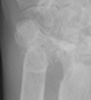

Advanced signs of RA include diffuse loss of joint space due to loss of cartilage. There can also be marginal or central erosions and severe joint deformities. Subluxations and dislocations may lead to ulnar deviation at the MCP joints and radial deviation at the radiocarpal articulations of the wrists. Erosive changes are also noted at the distal ulna and radial styloid. Joint deformities seen in RA include a Boutonniere deformity (flexion at the PIP joint and hyperextension at DIP joint) and a Swan-neck deformity (hyperextension at the PIP joint and flexion at the DIP joint). In severe cases, there may be radiographic findings of ankylosis at the proximal interphalangeal and metacarpophalangeal joints.

The differential includes SLE and seronegative spondyloarthropathies such

as ankylosing spondylitis, psoriatic arthritis, and Reiter's arthritis. The

DIP joints are often not affected in RA. Furthermore, the radiographic findings

of subchondral sclerosis and osteophytosis are often absent.